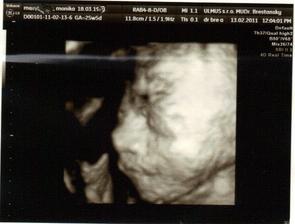

krasne 3D sono 🙂